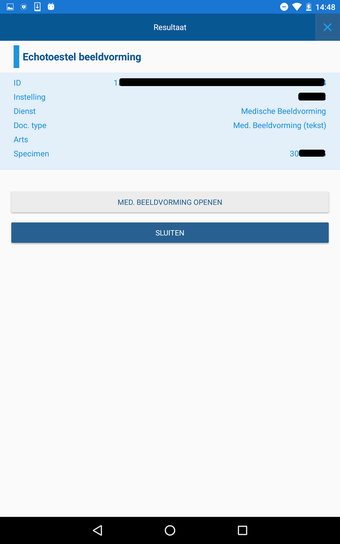

CoZo permet aux patients de prendre une part active dans leur propre santé et d'être traités comme des participants actifs dans le processus de soins. Les patients peuvent utiliser l'application pour enregistrer leurs données de santé, qu'ils peuvent ensuite partager avec leurs médecins. Les médecins peuvent utiliser l'application pour enregistrer l'historique médical de leurs patients, poser un diagnostic et suggérer un plan de traitement.